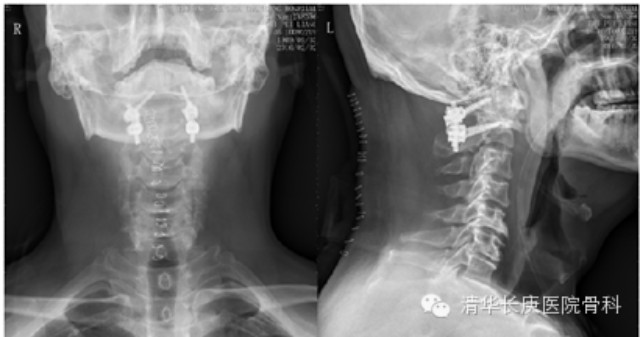

2016年1月26日上午9时,手术开始。在麻醉科张欢主任、赵艳军医师静吸复合全麻及监测保驾护航下,术中电生理监测,颅骨牵引,先行前路经口手术。使用颈椎间盘镜下高速磨钻一点点去除增生的骨赘和脱位的齿状突,将卡压在接近延髓的高位颈脊髓上的增生硬化骨块完美去除,彻底松解;再改俯卧位Mayfield头架牵引固定下行后路C1、2经椎弓根螺钉内固定、植骨融合术(图3)。手术顺利,出血极少。由于手术精准微创,术后患者症状缓解,且未出现经口手术较为常见的咽后壁水肿、感染等并发症,恢复非常顺利,数日后即出院返回山东老家过年。

图3、术后X光:压迫脊髓之脱位齿状突及增生切除,减压充分,复位及固定位置满意